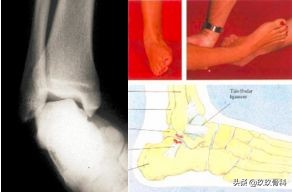

辅助检查

- X线 踝关节正侧位(必要时应加照踝穴位)

- B超

- MRI

应力位片

4.踝的外旋损伤(下胫腓骨间韧带损伤)

损伤机制:踝的外旋扭转引起胫腓骨之间韧带撕裂(滑雪损伤)

损伤病理:胫腓骨之间韧带撕裂

诊断:体检—疼痛肿胀压痛的部位在踝的前上方;X线—踝内旋20°正位